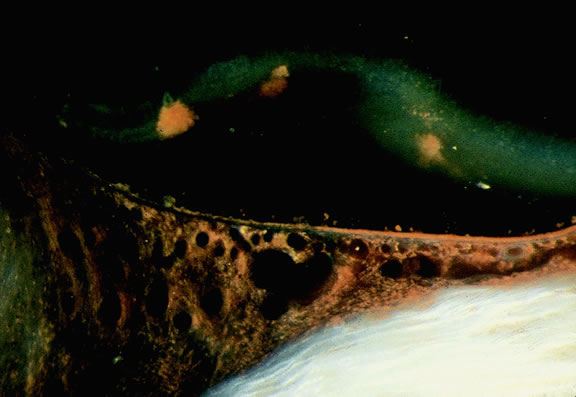

Many choroidal melanomas have a characteristic mushroom or collar button configuration that results when the tumor breaks through Bruch's membrane (Figs. 19, 20, 21, and 22). In such cases there is often secondary choroidal, subretinal, or vitreous hemorrhage. Dilated, intrinsic vessels often are evident in the mushrooming dome of nonpigmented melanomas. The vessels are obscured in more pigmented tumors.48

Fig. 20. Gross photo of mushroom-shaped choroidal melanoma. Amelanotic dome of melanoma anterior to break in Bruch's membrane elevates and detaches retina. Mushrooming head of tumor has a rough papillary surface and contains many vessels.